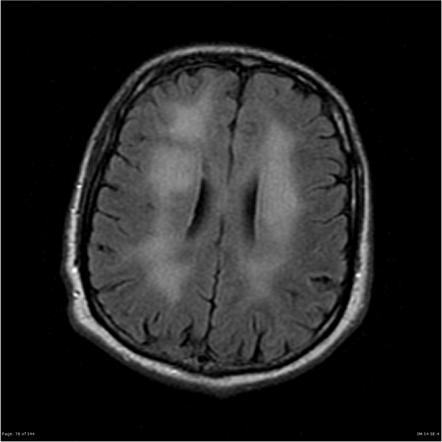

Imaging findings typical of HAD

Diffuse cerebral atrophy

Sometimes white matter changes and abnormalities are present in the thalamus and basal ganglia